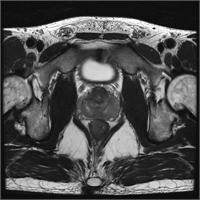

頚動脈プラーク